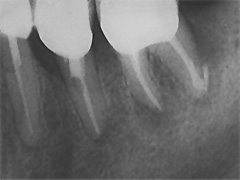

Dieser Zahn wurde schon geraume Zeit zuvor von einer Kollegin im Notdienst eröffnet und anschlies­send mit einer aufwendigen Amal­gamrestauration ästhetisch an­sprechend wieder verschlossen. (Bild 1) Uns blieb noch WK/WF, was bei massiver Überstopfung der hin­teren Wurzel auch gelang (Bild 2).

"Überstopfen ist immer noch besser als Unterstopfen" laut Koçkapan. OK, hier wurde des Guten aber ganz eindeutig zuviel getan.

Also direkt neben dem Zahn das Zahnfleisch ein wenig angehoben und zur Seite gedrängt und dann mit einem scharfen Löffel den Überschuss vollständig entfernt.

Schon 8 Monate später ist eine deutliche Verbesserung der Gesamt­situation unverkennbar (Bild 3). Verlorengegangene Knochensubstanz wurde in Teilen schon wieder aufge­baut, doch ist noch gar nichts entschieden. Schaun mer also ma'.

Abrechnungstechnisch hat der Mut zur WR an 38 gefehlt, deshalb nur EXZ1.